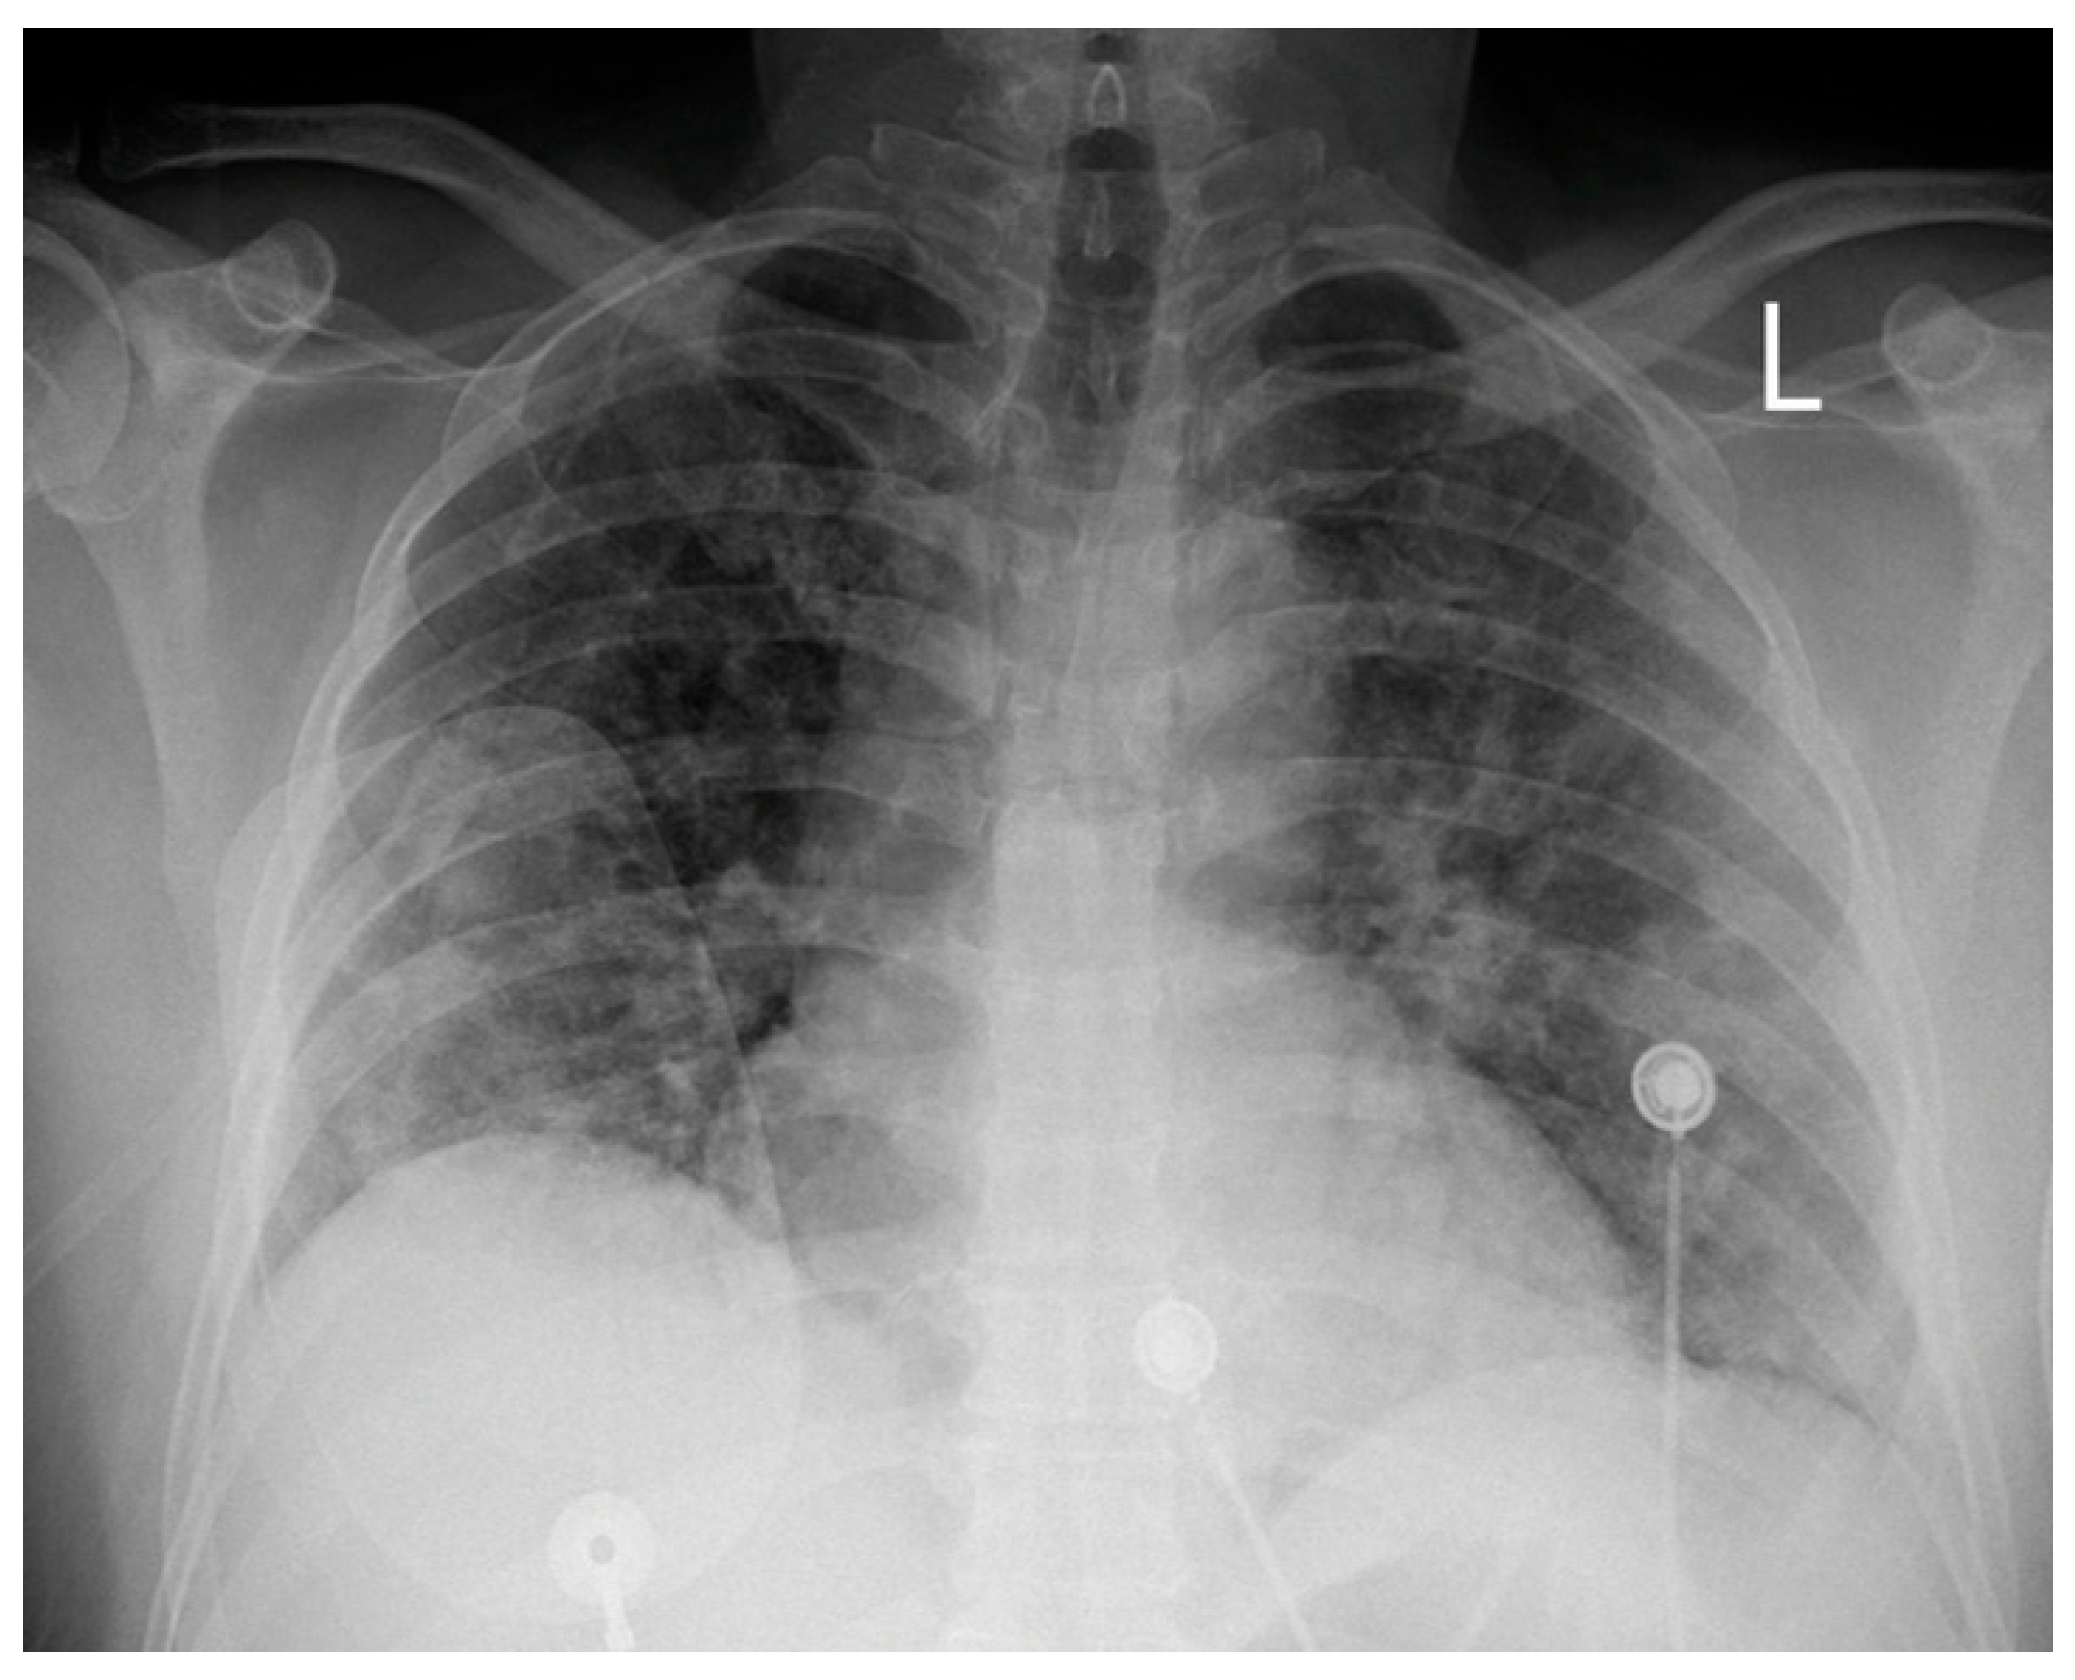

A 51-year-old white male with a medical history of hypertension was admitted to our hospital’s COVID-19 clinic due to a recent onset of fever, cough, and respiratory distress along with positive real-time polymerase chain reaction assay for SARS-CoV-2 infection. He was initially administered with oxygen via high-flow-nasal-cannula, dexamethasone, remdesivir, tocilizumab bolus, and fondaparinux for thromboprophylaxis. On day 7, while in severe respiratory distress (Figure 1) supported with a continuous positive airway pressure helmet, the patient complained of retrosternal chest pain radiating in his left arm with concomitant diaphoresis. His blood pressure was 140/80 mmHg and his pulse was 55 beats per minute. Lung auscultation revealed rales in both lungs, while the rest of the physical exam was normal. An electrocardiogram (ECG) was immediately obtained, which demonstrated normal sinus rhythm and 2 mm ST-segment elevation in leads II, III, AVF, V5, and V6 along with ST-segment depression in leads V1–V2.

Figure 1. Chest X-ray on the day of the episode; (L: left side).